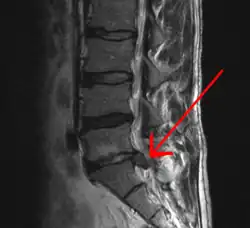

![]() Obraz dyskopatii w badaniu MRI |

Termin dyskopatia odnosi się także do potocznej nazwy przepukliny jądra miażdżystego tarczy międzykręgowej kręgosłupa. Polega na uwypukleniu jądra miażdżystego, które powoduje ucisk i drażnienie korzeni rdzeniowych, rdzenia kręgowego lub innych struktur kanału kręgowego. Mechanizm drażnienia jest dwojaki. Po pierwsze dolegliwości bólowe powodowane są przez ucisk mechaniczny. Drugim elementem mogącym wywoływać bodźce bólowe jest niskie pH jądra miażdżystego spowodowane ubogą w tlen przemianą materii.